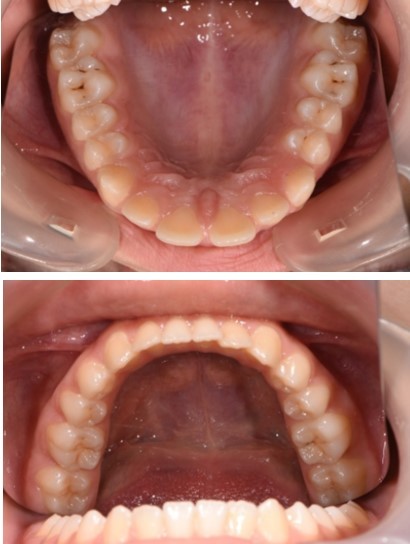

Figure 4.Treatment start - Orthodontic appliance on the upper arch, Roth 022" prescription.

Treatment started with orthodontic appliances on the upper arch, Roth 022" prescription. In order to achieve a better retraction of the upper teeth, first bicuspids were extracted. Retraction of the upper incisors with elastics chains placed from crimpable hooks to orthodontic implants.